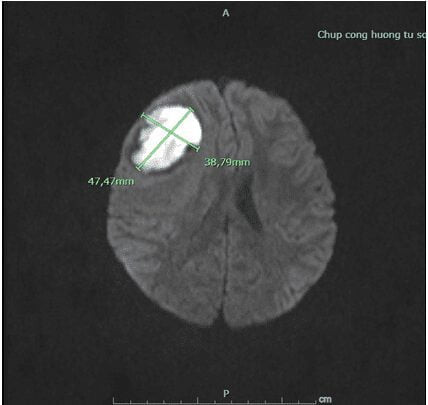

Gia đình cho cháu đi khám tại bệnh viện huyện nghi ngờ u não và được chuyển đến Bệnh viện tỉnh.Tại đây cháu được khám, chụp cộng hưởng từ và được kết luận là áp – xe não do bệnh tim bẩm sinh. Khối áp -xe kích thước khoảng 4 x 5 cm và có viền phù não xung quanh.

| Khối áp xe não trên phim cộng hưởng tử |